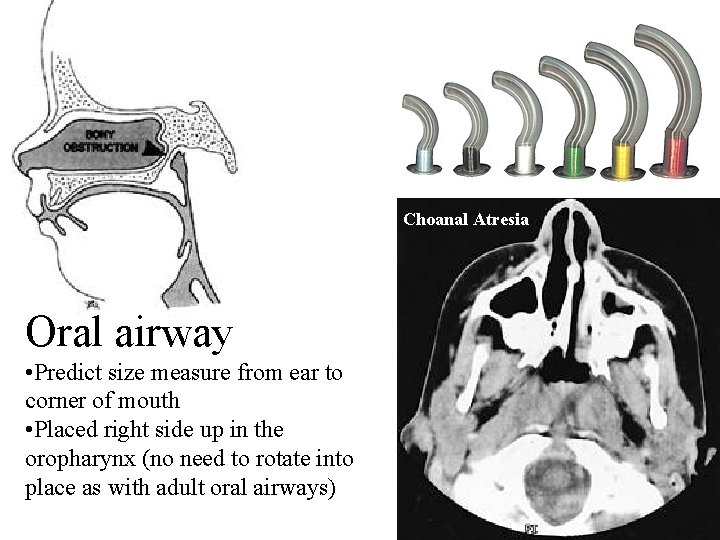

Oral airway • Used for: • Micrognathia (pictured here) • Pierre Robin • Choanal atresia • airway may cause gagging

Choanal Atresia Oral airway • Predict size measure from ear to corner of mouth • Placed right side up in the oropharynx (no need to rotate into place as with adult oral airways)